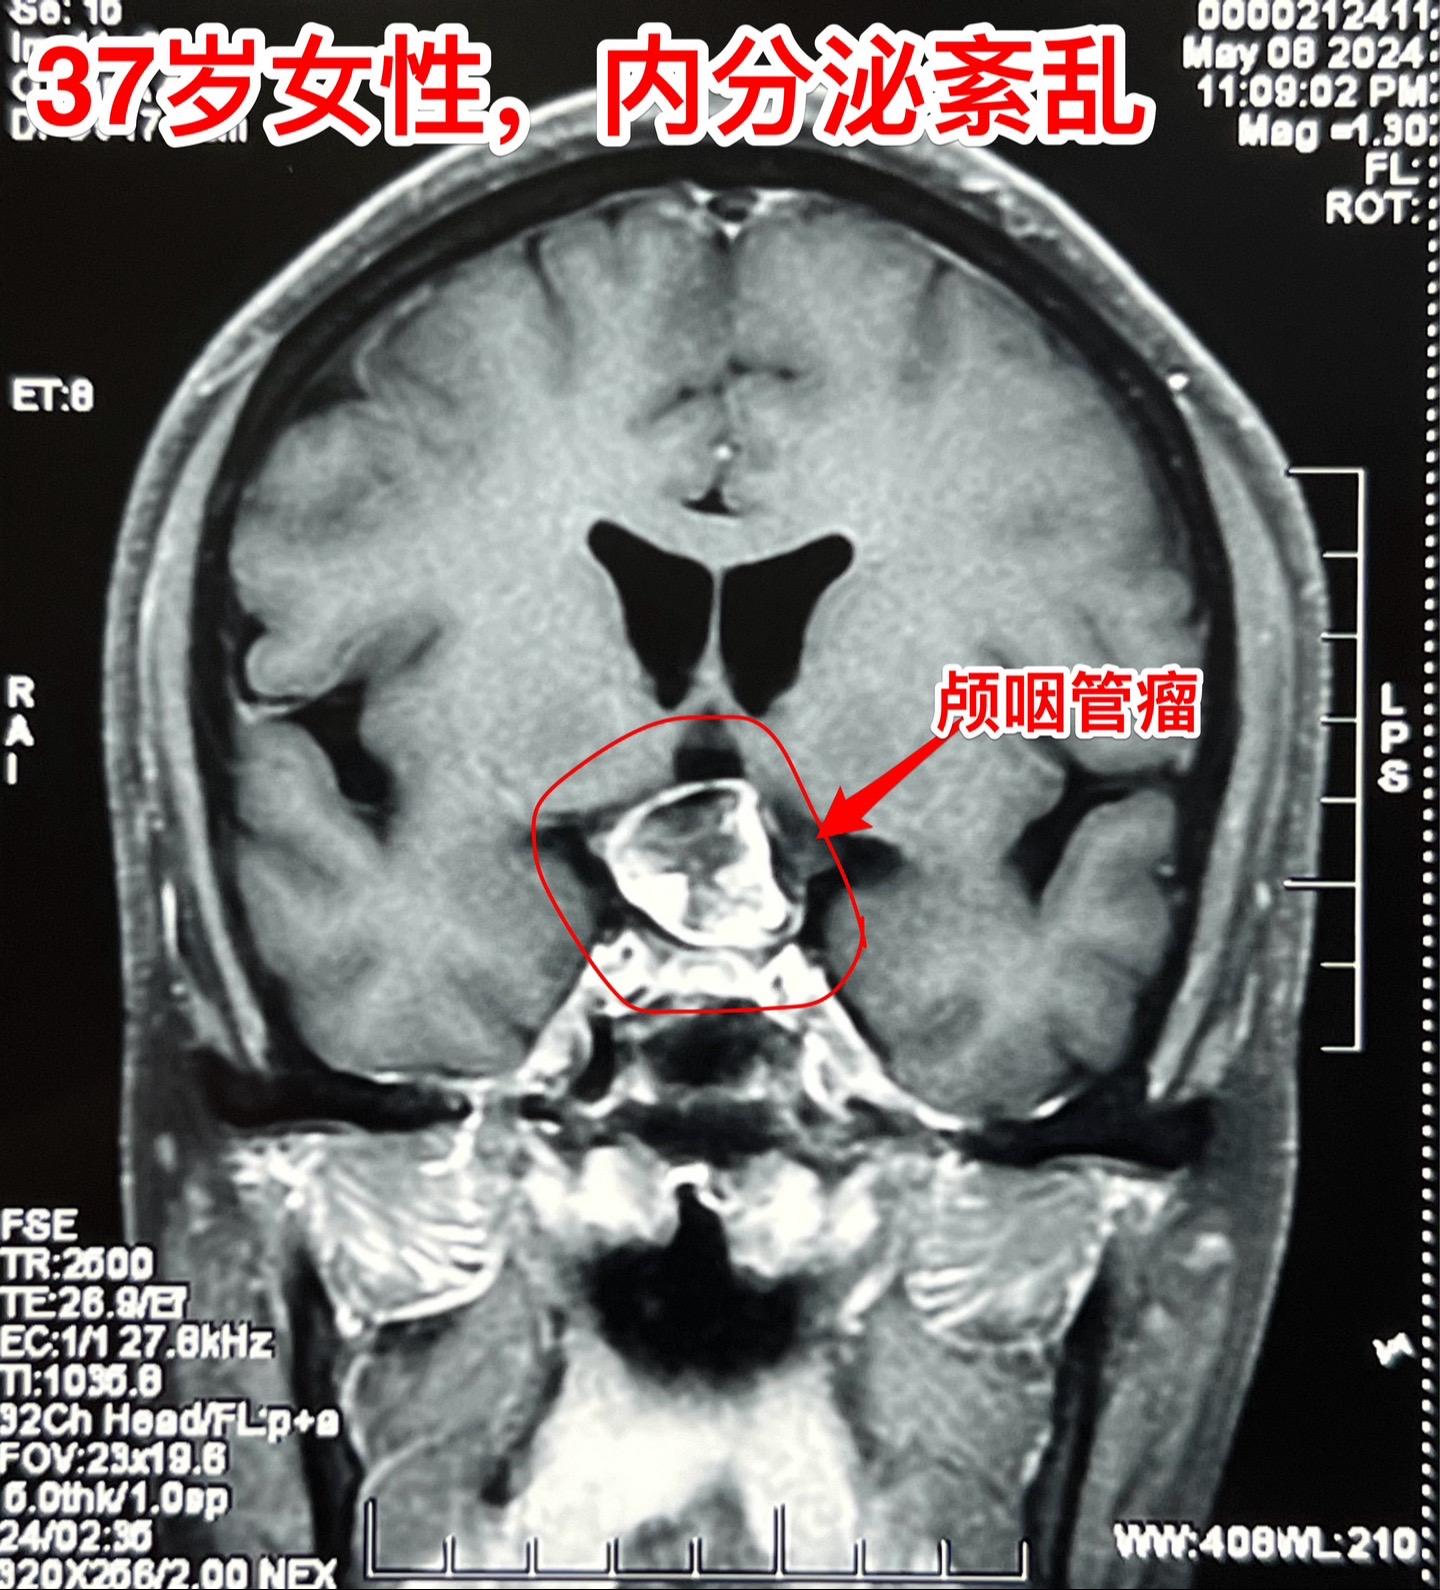

5月16日两个颅咽管瘤手术。五一假期后开展的手术都是颅咽管瘤切除手术。经常一天作两个颅咽管瘤手术!这样的劳动强度有点大! 5.16一天两个颅咽管瘤手术,肿瘤有相似的特征,两个都有大块的钙化斑;都是从垂体柄侵入垂体中;手术方式也相似-经额底纵裂入路。 手术后两个病人都顺利从ICU转移到普通病房。

5月16日两个颅咽管瘤手术。五一假期后开展的手术都是颅咽管瘤切除手术。经常一天作两个颅咽管瘤手术!这样的劳动强度有点大! 5.16一天两个颅咽管瘤手术,肿瘤有相似的特征,两个都有大块的钙化斑;都是从垂体柄侵入垂体中;手术方式也相似-经额底纵裂入路。 手术后两个病人都顺利从ICU转移到普通病房。颅咽管瘤